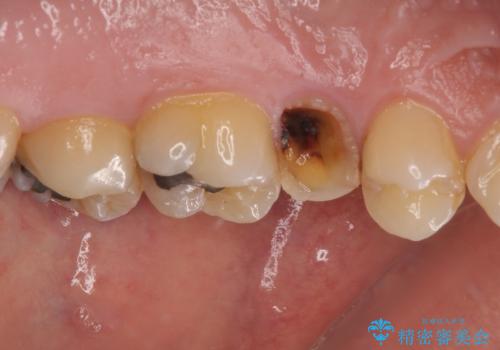

強い痛みのあった歯は、既に神経組織が失活しており根管治療が必要でした。

反対側の歯は、歯根だけが歯肉に埋もれて残っている状態のため、抜歯が必要な状態でした。

歯根だけとなっている歯はインプラントに、神経組織の失活している歯は根管治療を行い、いずれもオールセラミッククラウンにて補綴治療を行うこととしました。